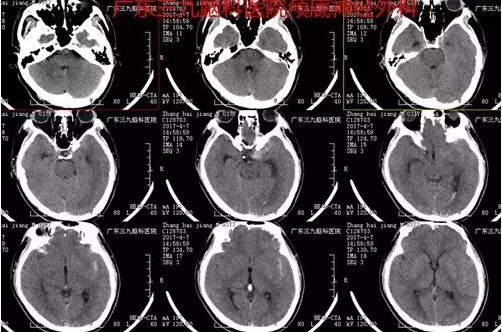

图1:术前CTA提示左侧颈内动脉末端动脉瘤

图2:术前CT提示蛛网膜下腔出血